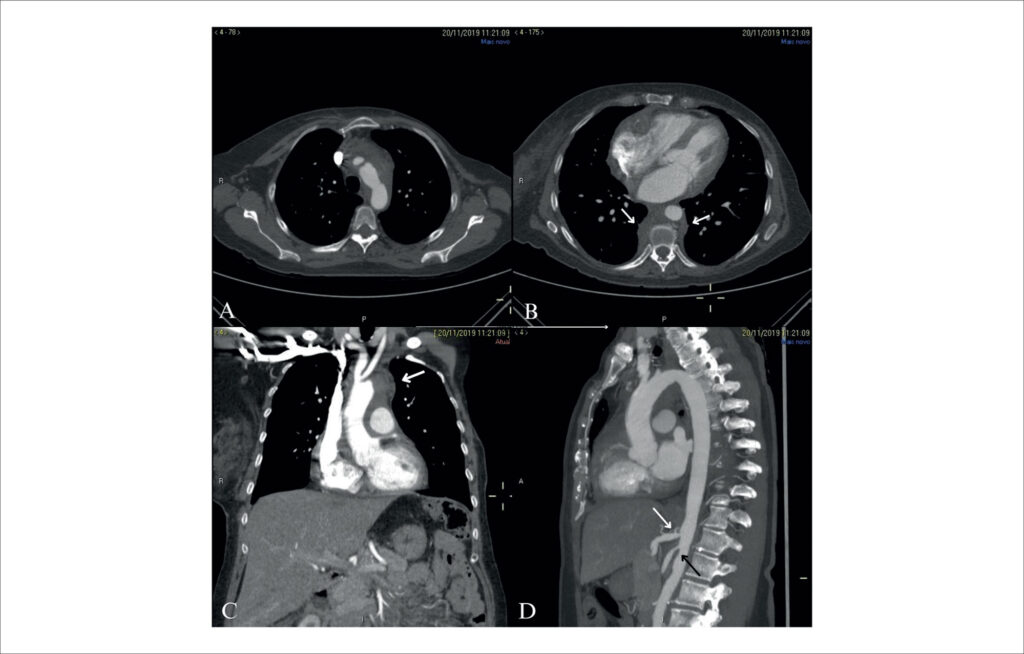

Cardiac Tamponade: Initial Clinical Presentation of Fibrosing Mediastinitis

Fibrosing mediastinitis (FM) is a rare condition characterized by the proliferation of fibrotic tissue in the mediastinum, presenting as a concentrated mass or diffuse infiltration., Clinical conditions can range from benignity to obstruction of critical mediastinal structures, such as vessels, airways, and the esophagus. Common complaints are cough, dyspnea, recurrent pulmonary infection, hemoptysis, and pleuritic pain. Pericardial involvement is not frequently reported in the literature. In this article, we describe a rare case of major pericardial effusion with cardiac tamponade as an initial presentation of FM in a patient with cancer.